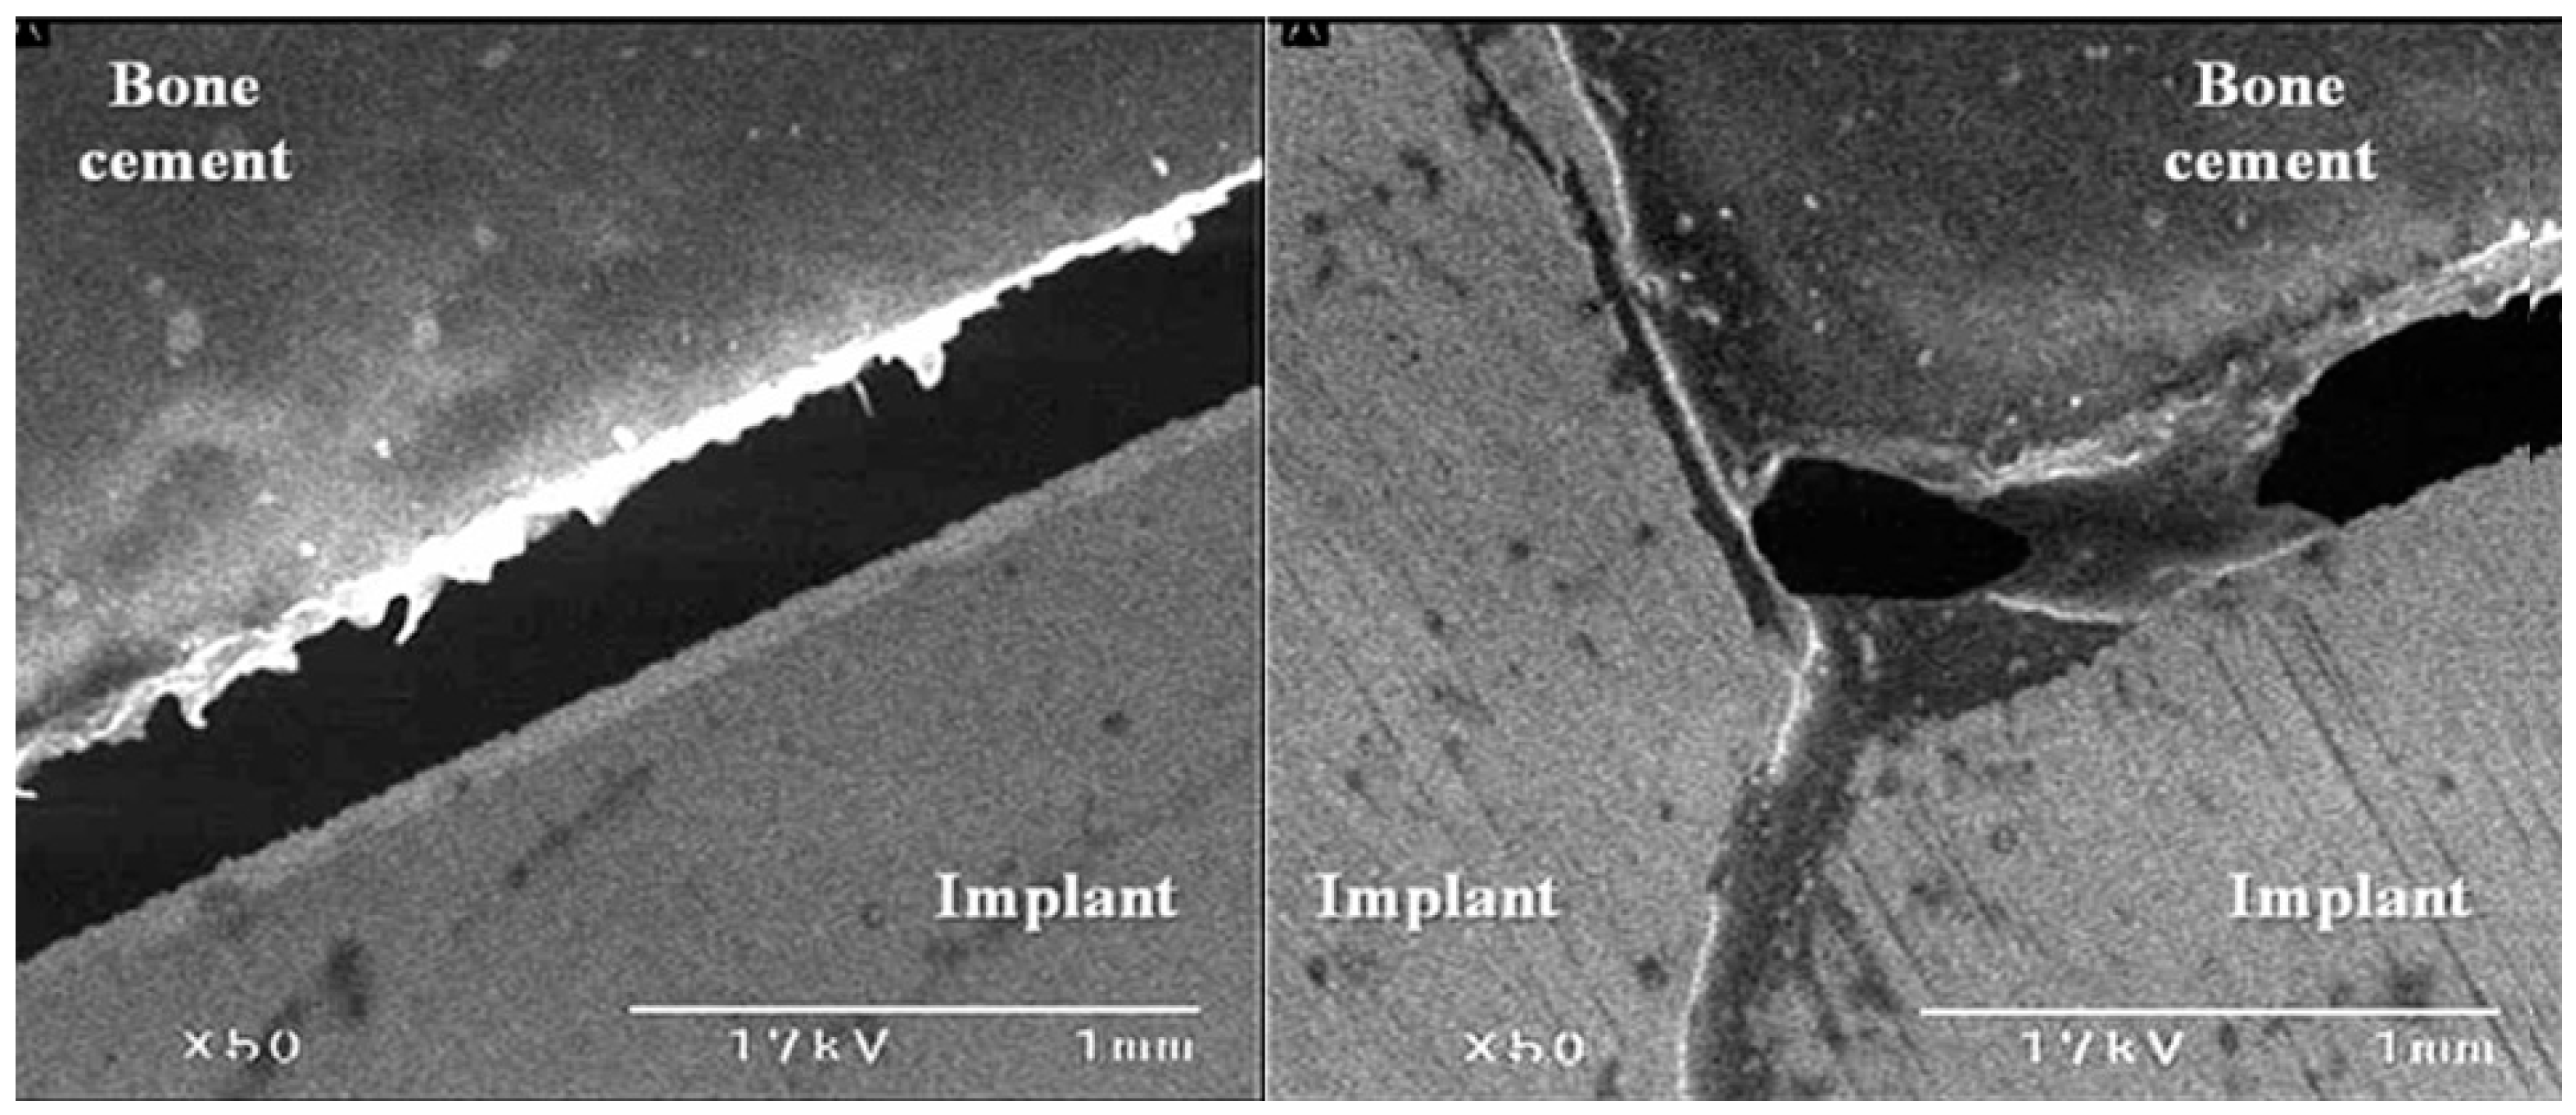

3.3. The Bond Strength at the Bone–Cement Interface

4. Discussion